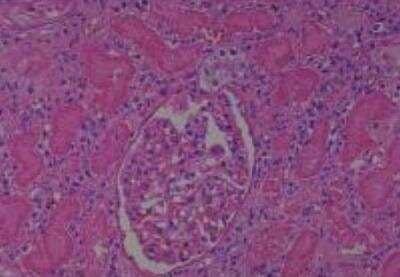

Scientific Data Images for Human Multi Tissue MicroArray (Normal Adjacent)

Hematoxylin & Eosin Stain: Human Common Tissue MicroArray (Normal Adjacent) [NBP2-30215] - 102. Stomach